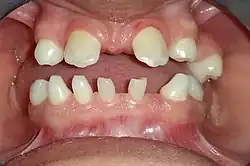

| Anodontia view of patient showing oligodontia and conical teeth | |